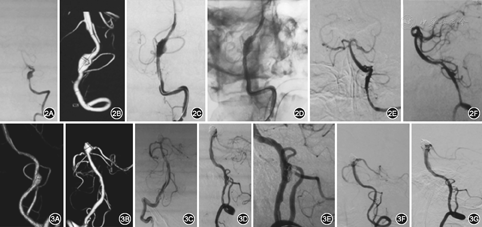

典型病例介绍:例1.患者女,55岁,因突发头痛12 h,加重伴恶心呕吐、意识丧失3 h入院,颅脑CT检查显示SAH,DSA检查显示PICA前型DAVA,行动脉瘤+载瘤动脉近端栓塞术,术后患者神志逐渐转清,言语正确,四肢活动正常,改良RANKIN量表(mRS)评分1分,见图1。例2.患者男,48岁,因突发头晕11 d入院,查体无明显阳性体征,颅脑CT检查未见颅内出血,DSA检查显示,PICA中型DAVA,行3层支架置入术,术后患者症状消失,神志清,言语正确,四肢活动正常,mRS评分0分,见图2。例3.患者男,70岁,因突发剧烈头痛伴恶心、呕吐8 d入院,颅脑CT检查显示SAH,DSA检查显示PICA后型DAVA,行支架辅助微弹簧圈栓塞术,术后患者病情稳定,神志清,言语正确,四肢活动正常,mRS评分0分,见图3。